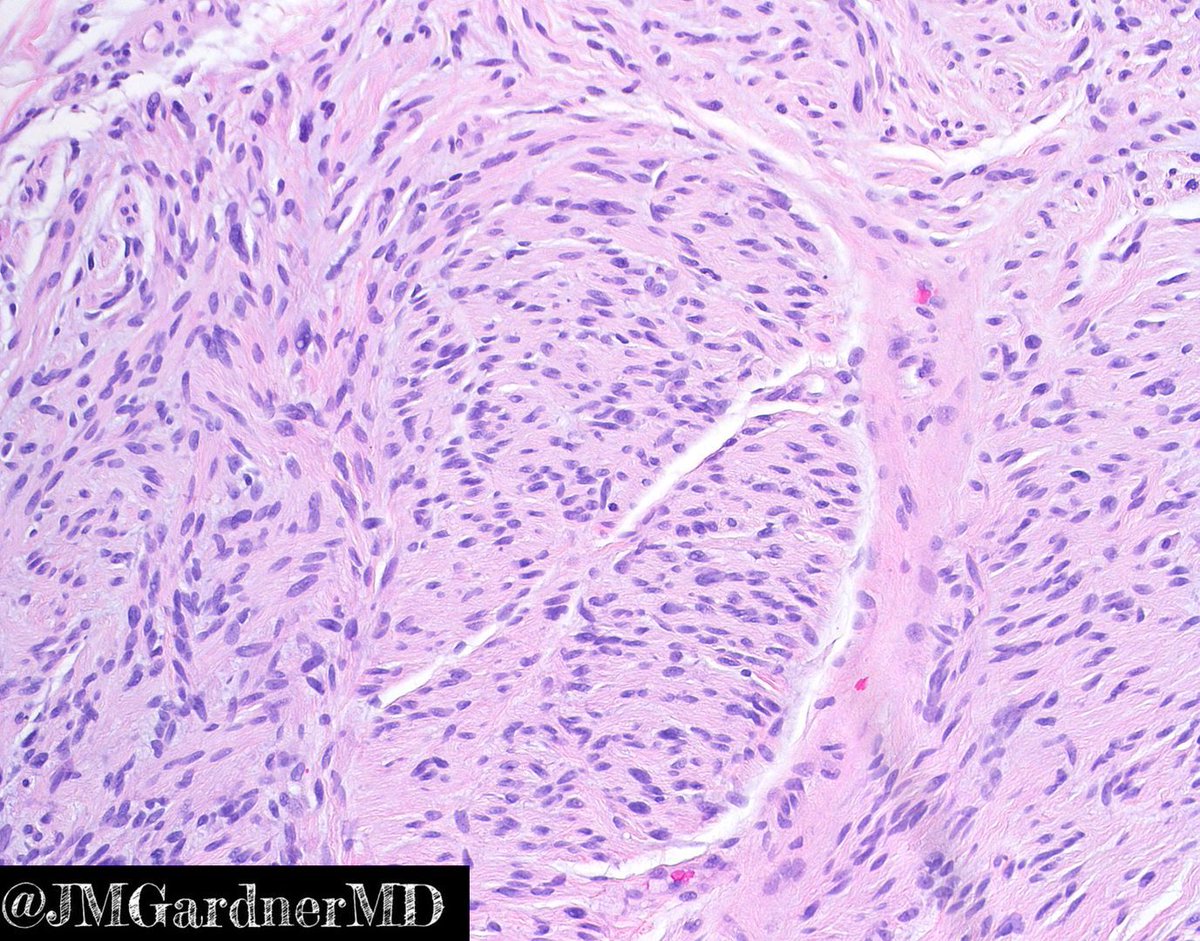

Apocrine differentiation in basal cell... Jerad Gardner, MD Basal Cell Carcinoma Jerad Gardner — sample pathology report templates for basal cell carcinoma: — basal cell carcinoma (bcc) is the most common human cancer worldwide, and is a subtype of nonmelanoma skin. — basal cell carcinoma (bcc) arises from the interfollicular or follicular epithelium. as the most common human cancer worldwide and continuing to increase in incidence, basal cell carcinoma. Basal Cell Carcinoma Jerad Gardner.